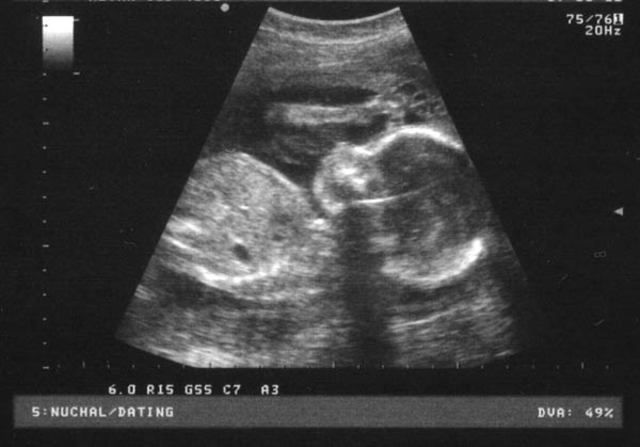

El huevo implantado en la mucosa uterina se divide en dos partes que darán lugar a la placenta y al feto.

Tiene una forma alargada y mide aproximadamente 1,25 mm y presenta un tubo neural, que dará lugar a la formación del sistema nervioso. Tres capas de células formarán la cabeza, el tronco y las extremidades del embrión. Su cuerpo, en forma de coma deja entrever una cabeza y una cola.

En este periodo, su corazón empieza a latir gracias a la fusión de dos vasos sanguíneos.